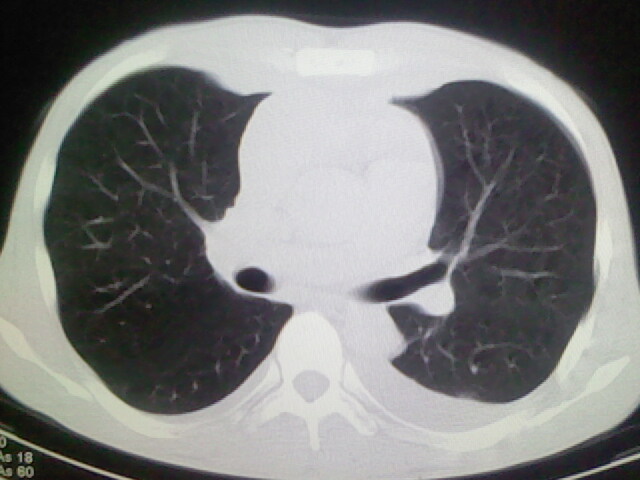

以下是引用杀毒软件在2008-9-3 6:11:00的发言:[br]侵袭性胸腺瘤------一般不侵到气管旁[br][br]考虑----纵隔淋巴瘤,心包及胸膜受累

以下是引用随光逐影在2008-9-3 7:07:00的发言:[br]1)考虑淋巴瘤可能。2)双侧胸腔积液(以左侧为甚)。3)心包积液。